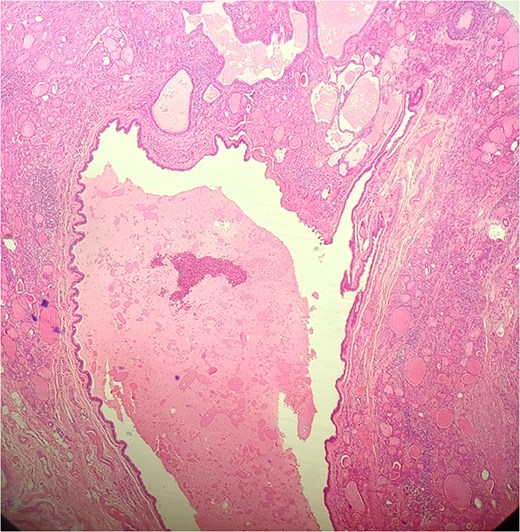

A 47-year-old woman with unremarkable medical history, presented with a 2 months history of neck mass along the midline. Physical examination revealed a 6 cm mobile, thyroid nodule without compressive symptoms. There was no associated erythema, fluctuance, tenderness or adhesion to adjacent structures. There was also no associated cervical lymphadenopathy. The rest of the physical exam was unremarkable. Laboratory tests including TSH, FT3, and FT4 revealed normal levels. On cervical ultrasound, there were a 62 mm left toto-lobar nodule classified as EU-TIRADS3, and an 11 mm right nodule, also classified as EU-TIRADS3. Fine-needle aspiration cytology concluded to a benign lesion classified as BETHESDA II. The patient reported respiratory discomfort in the supine position, leading to the indication for a lobectomy. Gross examination of the specimen revealed a toto-lobular nodule with a colloid appearance. It was well-circumscribed by a thin and regular fibrous capsule. The nodule measured 4 × 6 cm and exhibited areas of fibrous, whitish remodeling, as well as hemorrhagic and cystic changes. On microscopic examination, the nodule corresponded to a macro vesicular adenoma altered by fibrosis and hemorrhage. It was surrounded by a thin, regular, and intact fibrous capsule. However, at the periphery of the nodule, adjacent to the thyroid pseudo capsule, a 1.2 cm cystic ductal structure was observed. It showed pseudostratified ciliated columnar and squamous epithelial lining associated with thyroid follicles in the surrounding stroma (Figs 1 and 2). These thyroid follicles were bland with no papillary nuclear atypia or invasion (Fig. 3). The cyst was filled with a thin eosinophilic material (Fig. 4) Lymphocytic thyroiditis of mild severity was identified in the rest of the thyroid tissue. Based on these findings, the diagnosis of macro vesicular thyroid adenoma with ITTGDC and lymphocytic thyroiditis was made. After the surgery, the patient developed temporary dysphonia.

HE × 4 incidental finding of cystic duct structure in the adjacent thyroid gland tissue.

HE × 20: The cyst was lining with pseudostratified ciliated columnar cells and circumscribed with thyroid follicle within the cystic wall.